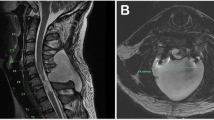

A healthy 29-year-old man developed Brown-Sequard syndrome immediately after performing a manipulation on his own cervical spine. Imaging showed large disc herniations at the levels of C4–C5 and C5–C6 with severe cord compression, so the patient underwent emergent surgical decompression. He was discharged to an acute rehabilitation hospital, where he made a full functional recovery by postoperative day 8.